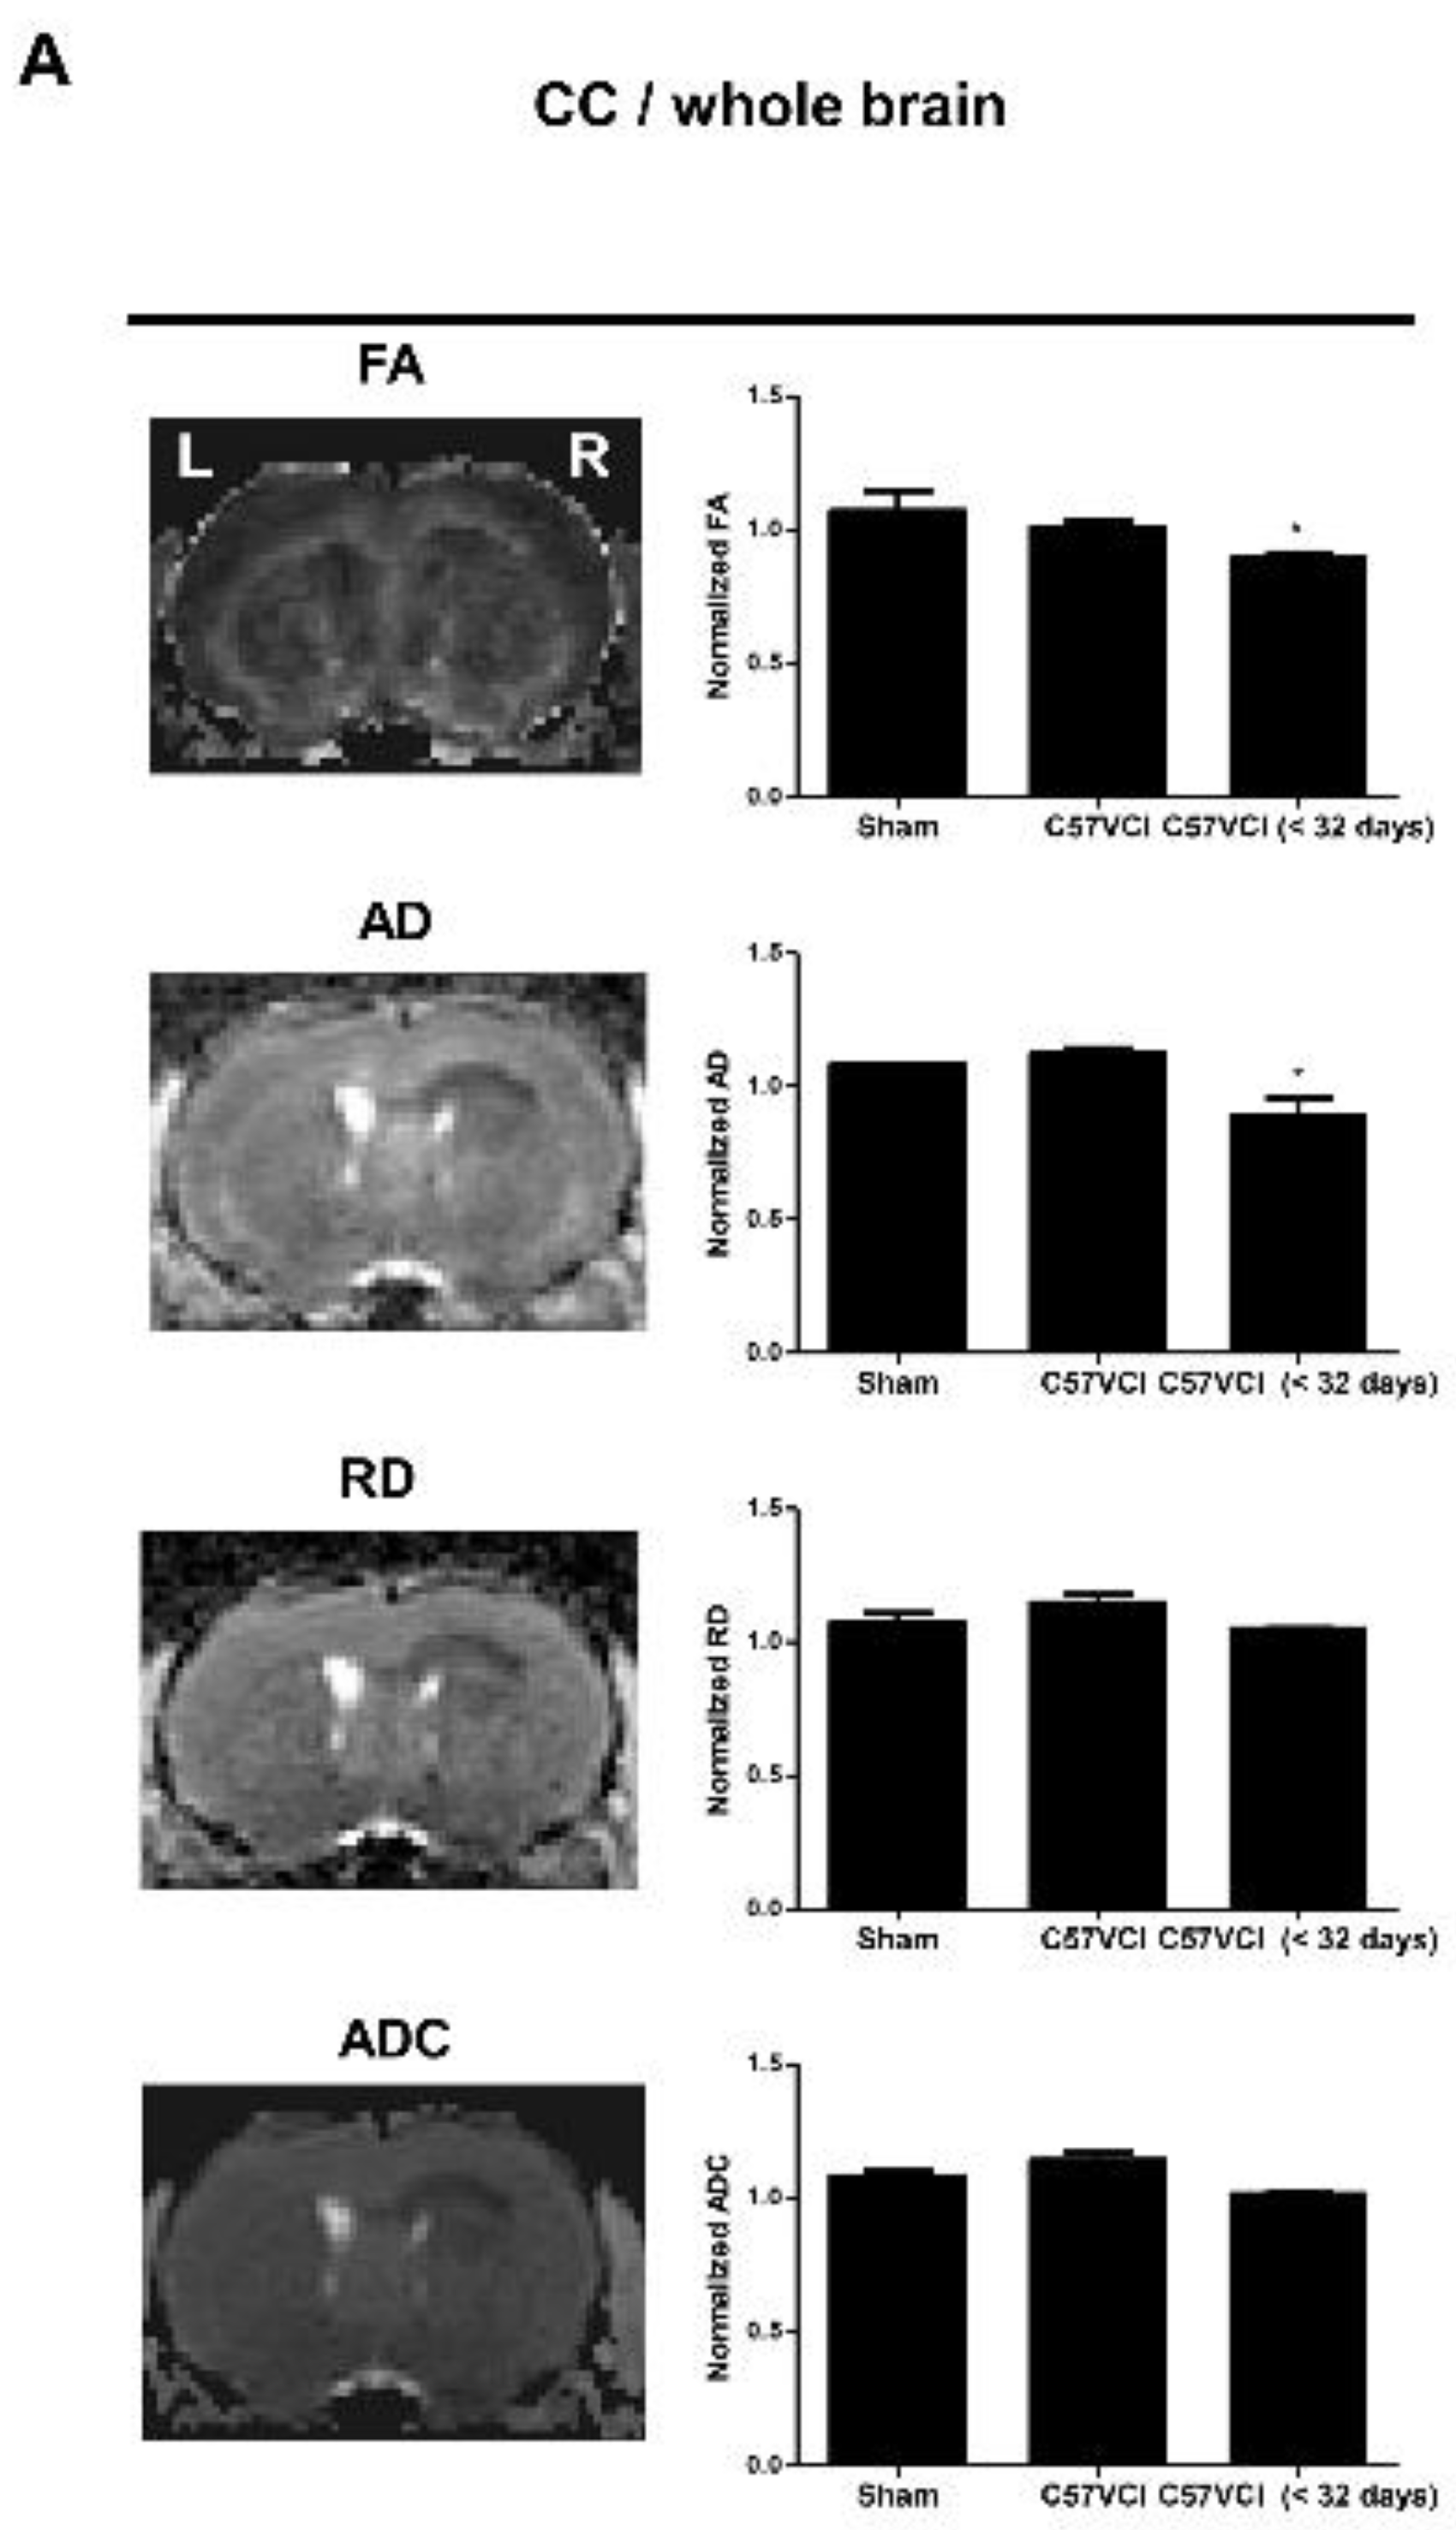

2.4. Differences in DTI Parameters Were Not Significant without the Presence of Infarcts